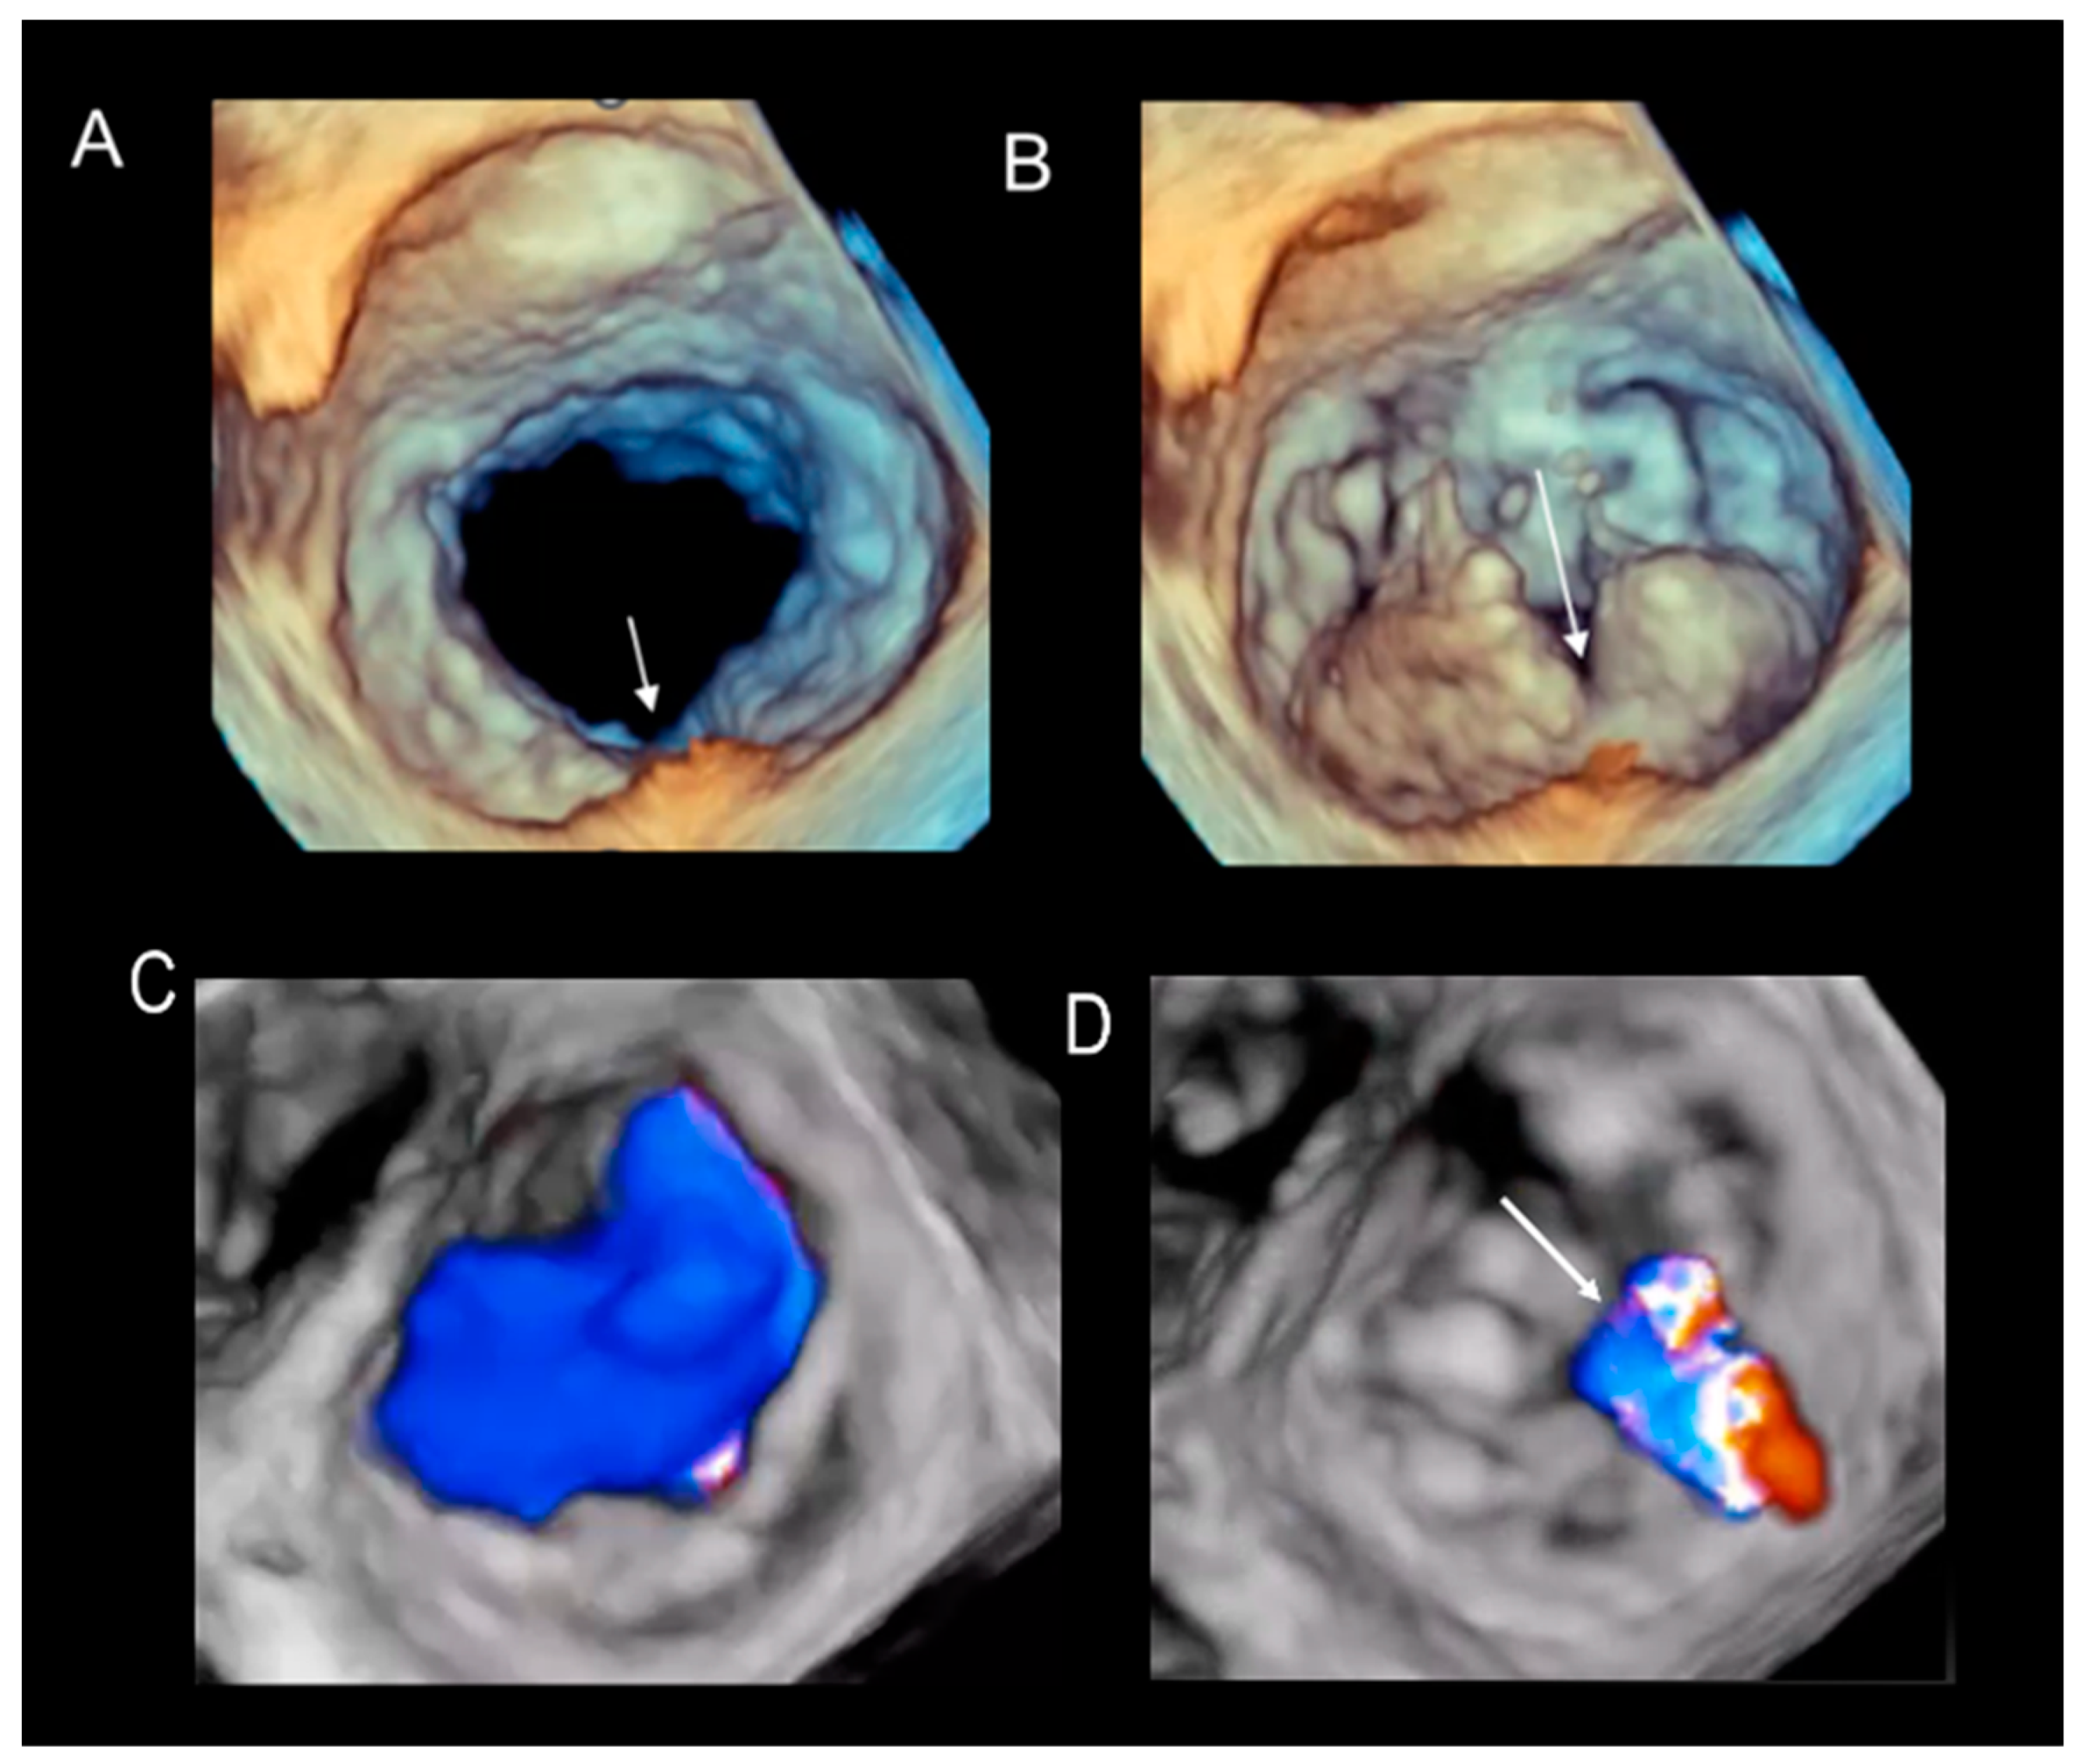

2.3. Scenario # 3

Cleft and Cleft-like Indentations

5. Assessment of Regurgitation Severity

Current Modalities

6. A New Tool